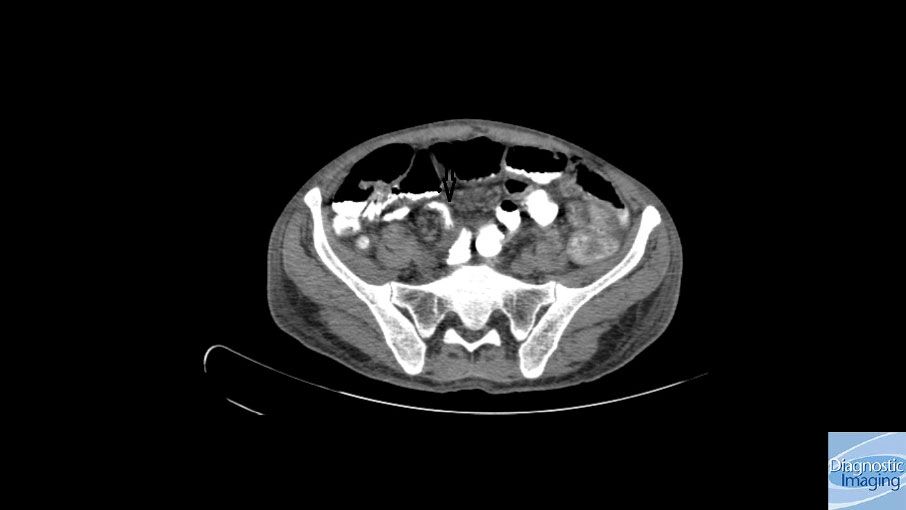

Case History: 45-year-old patient presented with complaints of vomiting for a few days.